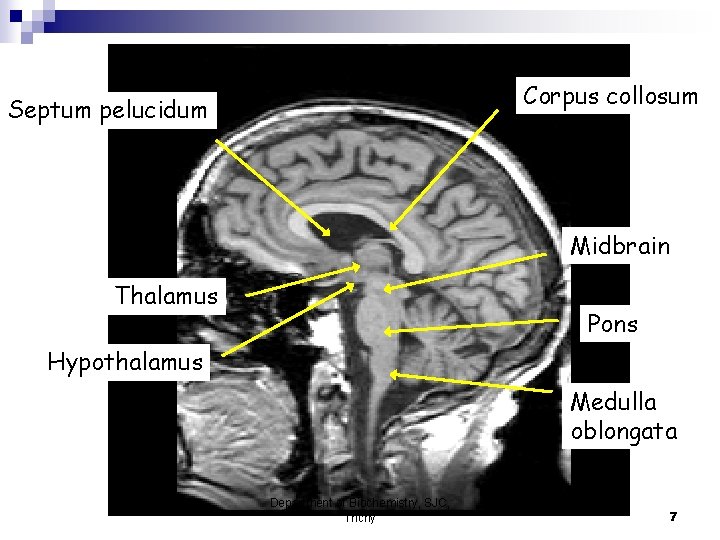

Corpus collosum Septum pelucidum Midbrain Thalamus Pons Hypothalamus Medulla oblongata Department of Biochemistry, SJC, Trichy 7